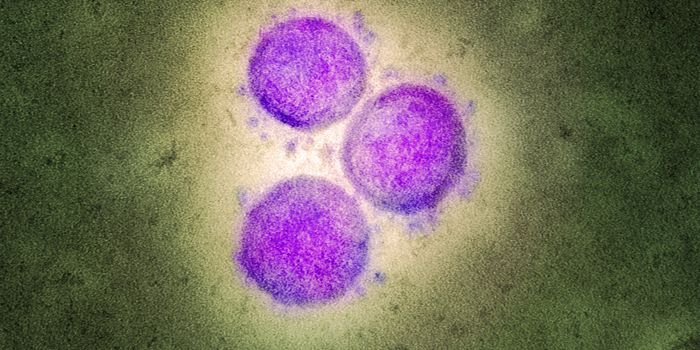

APR 27, 2020MicrobiologyThe pandemic virus that causes COVID-19 has now infected nearly 3 million people, and killed over 200,000.

MAY 10, 2021MicrobiologyThe pandemic virus SARS-CoV-2 has changed the world in devastating ways, taking hundreds of thousands of lives & new var ...

MAR 23, 2021Health & MedicineA pregnant woman infected with the pandemic virus SARS-CoV-2 passed the virus on to her unborn child through the placent ...